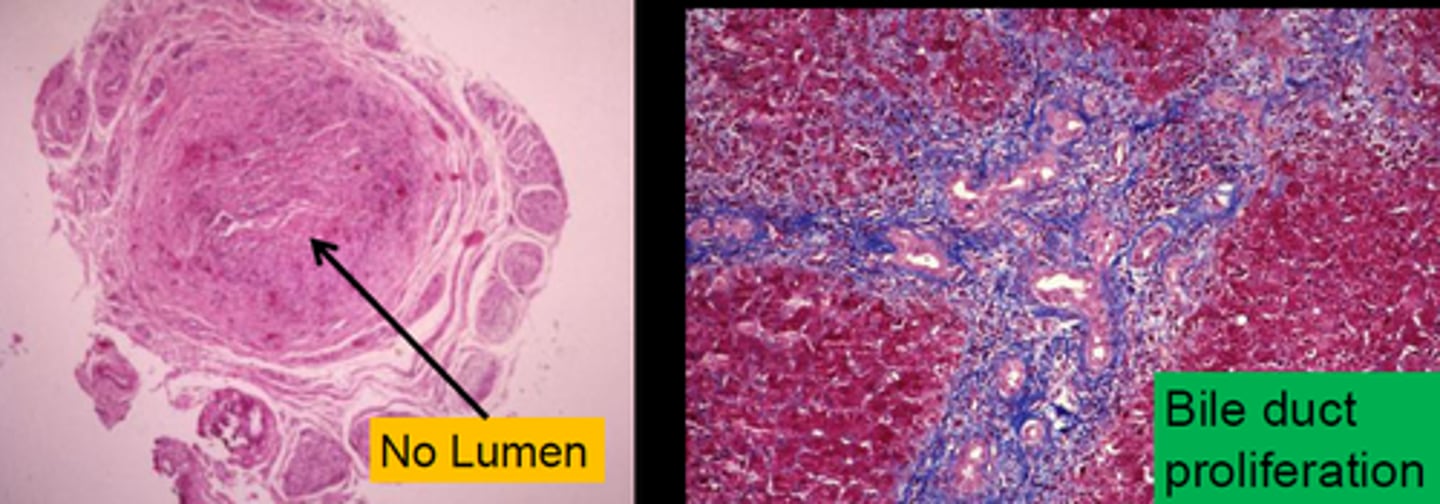

Biliary Atresia

Define Condition:

Complete or partial obstruction of extrahepatic biliary tree that occurs in first 3 months of life

-Hx:

> Fetal = congenital defect

> Perinatal (MC) = INFLAMMATION

-Sx/PE:

> Perinatal:

>> Persistent Jaundice after 2 wks of life

>> Dark Urine

>> Acholic (pale) Stools

>> Hepatomegaly

-Dx:

> Labs:

>> Elevated CB

>> Elevated GGT

> Biopsy

>> Perinatal:

>>> Inflammation

>>> Fibrosing stricture of hepatic or CBD

> Imaging:

>> US = A/w Absent/Abnormal Gallbladder

-Tx:

> MC reason for pediatric liver transplant

-Prog:

> MCC = DEATH from Liver Disease in early childhood

Primary Biliary Cholangitis (PBC)

Define Condition:

Autoimmune disease causing nonsuppurative, inflammatory destruction of small and medium intrahepatic bile ducts

> Biopsy:

>> Lymphoplasmacytic inflammation +/- granulomatous inflammation (florid duct lesion)

--> Loss of small intrahepatic ducts

--> Cholestasis/Cirrhosis